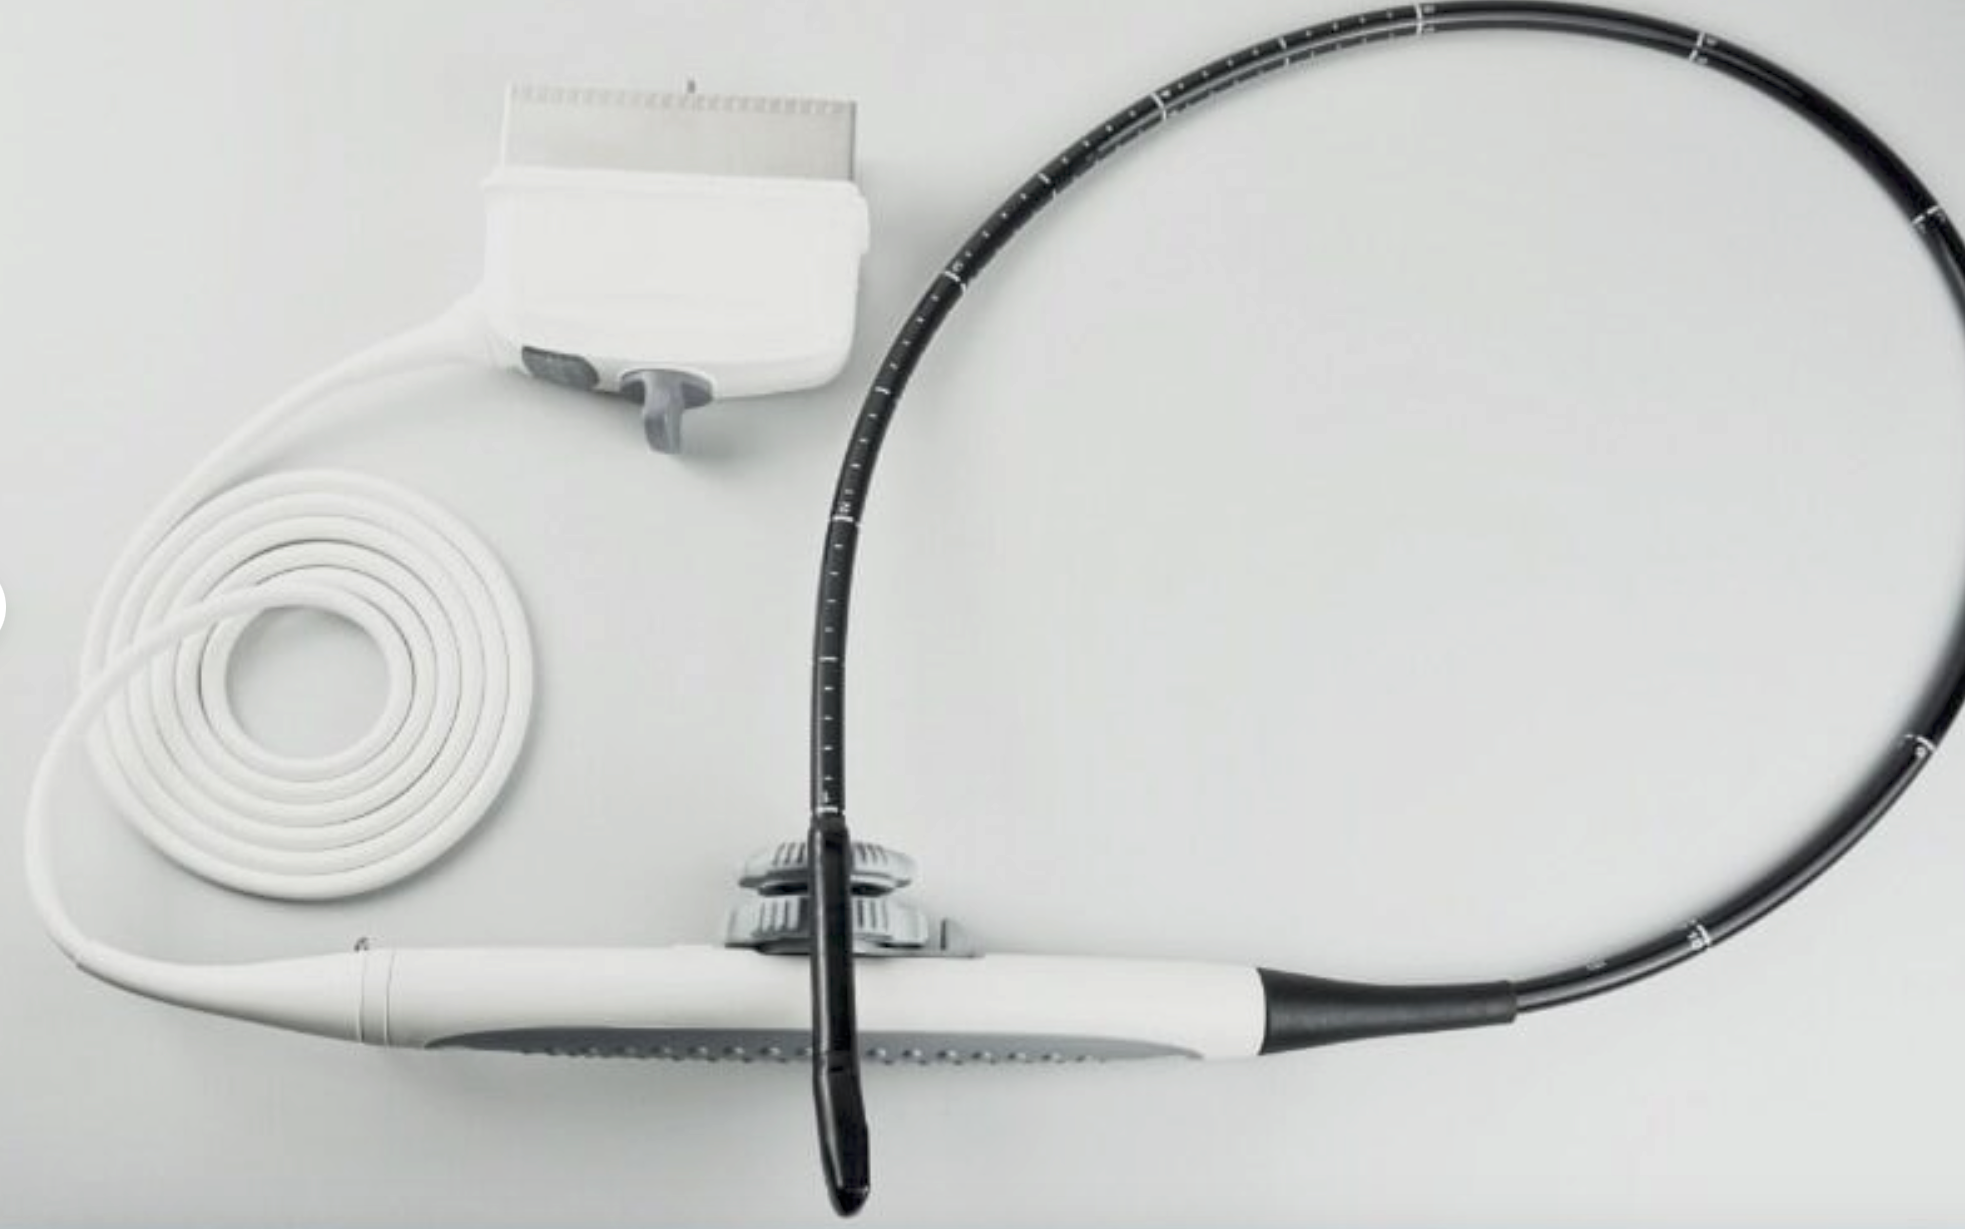

The laptop ultrasound scanner

utilizes state-of-the-art technology to provide clear and accurate imaging, essential for diagnosing various medical conditions. With both transvaginal and convex probes, it caters to a wide range of examinations. This versatility ensures healthcare professionals can perform different types of scans with a single device, making it incredibly efficient. Moreover, the scanner’s lightweight design allows for easy transport, which is particularly beneficial in emergency medical situations.